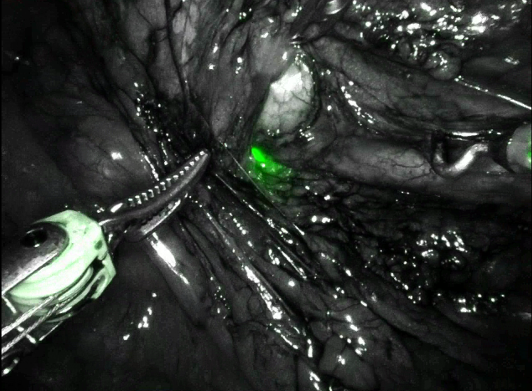

Intraoperatively, flexible ureteroscopy was performed to rapidly identify the left proximal ureter under near-infrared (Firefly) fluorescence, as well as to confirm luminal narrowing at the UPJ (Figure 3). There was no crossing vessel.

A new, dependent UPJ was fashioned over a ureteral stent as a non-transecting anastomosis (Figure 4). Intravenous indocyanine green (ICG) was given to confirm satisfactory perfusion to the repair prior to completion.

Intraoperative ureteroscopy is a helpful adjunct when a qualified assistant is available. In appropriate settings, this allows for rapid ureteral identification and stricture localization. Moreover, this practice preserves ICG for intravenous use to ensure satisfactory vascularity to the subsequent anastomosis.10 This is particularly salient for cases with impaired ureteral perfusion or those involving bowel harvest, as seen with re-operative procedures, abdominopelvic radiation, and urinary diversions. In our experience, visualizing the ureteroscope under near-infrared fluorescence can be difficult if the surrounding fibrosis is severe. Additional maneuvers include distending the affected ureter via an indwelling nephrostomy tube or pre-placed ureteral catheter, as well as manipulating a wire within the ureteral lumen while assessing for transmitted movement within the retroperitoneum.